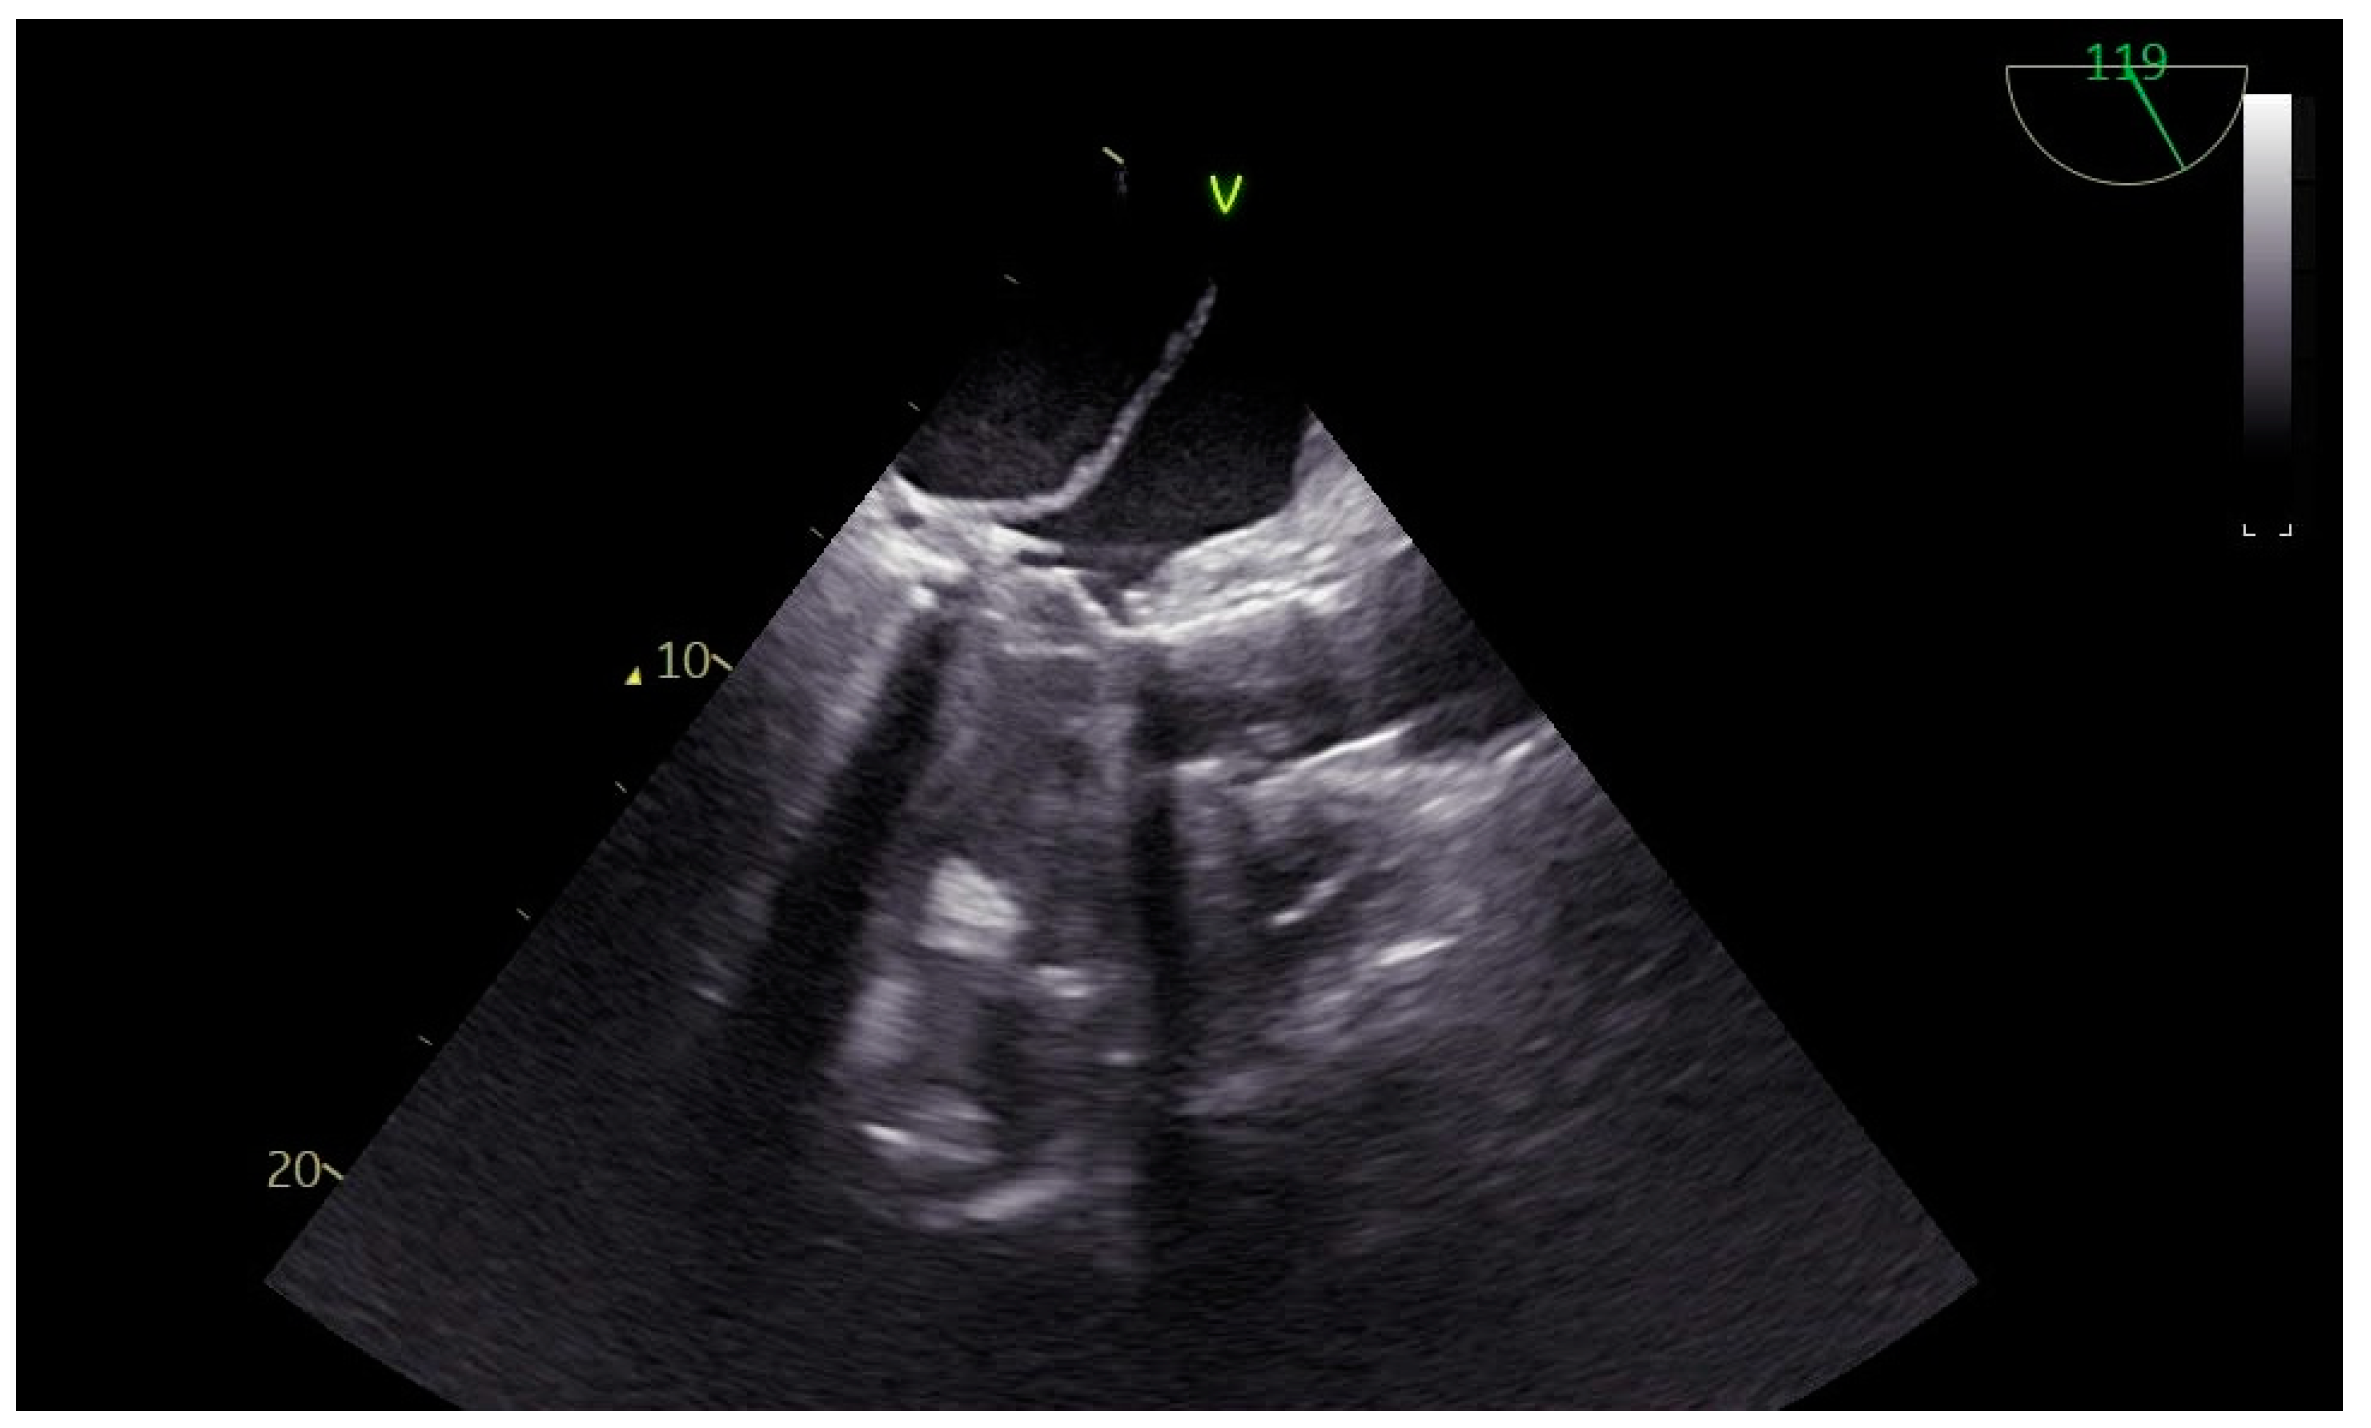

Left Atrial Dissection After Mitral and Aortic Valve Replacement: The Importance of Early Diagnosis of a Rare Entity

2. Case Presentation